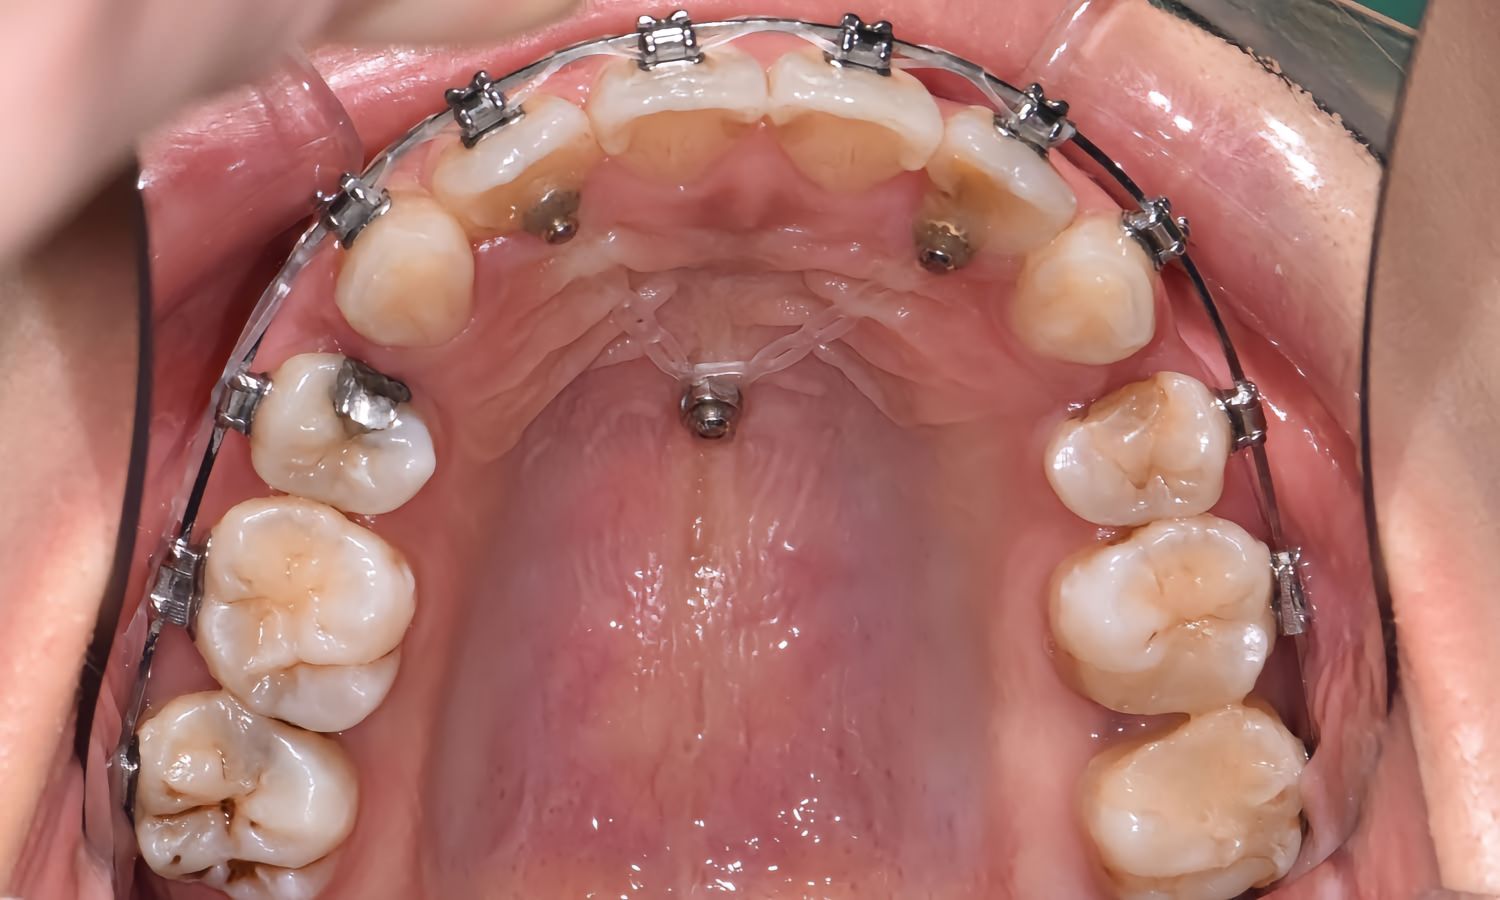

正畸支抗钉关闭间隙